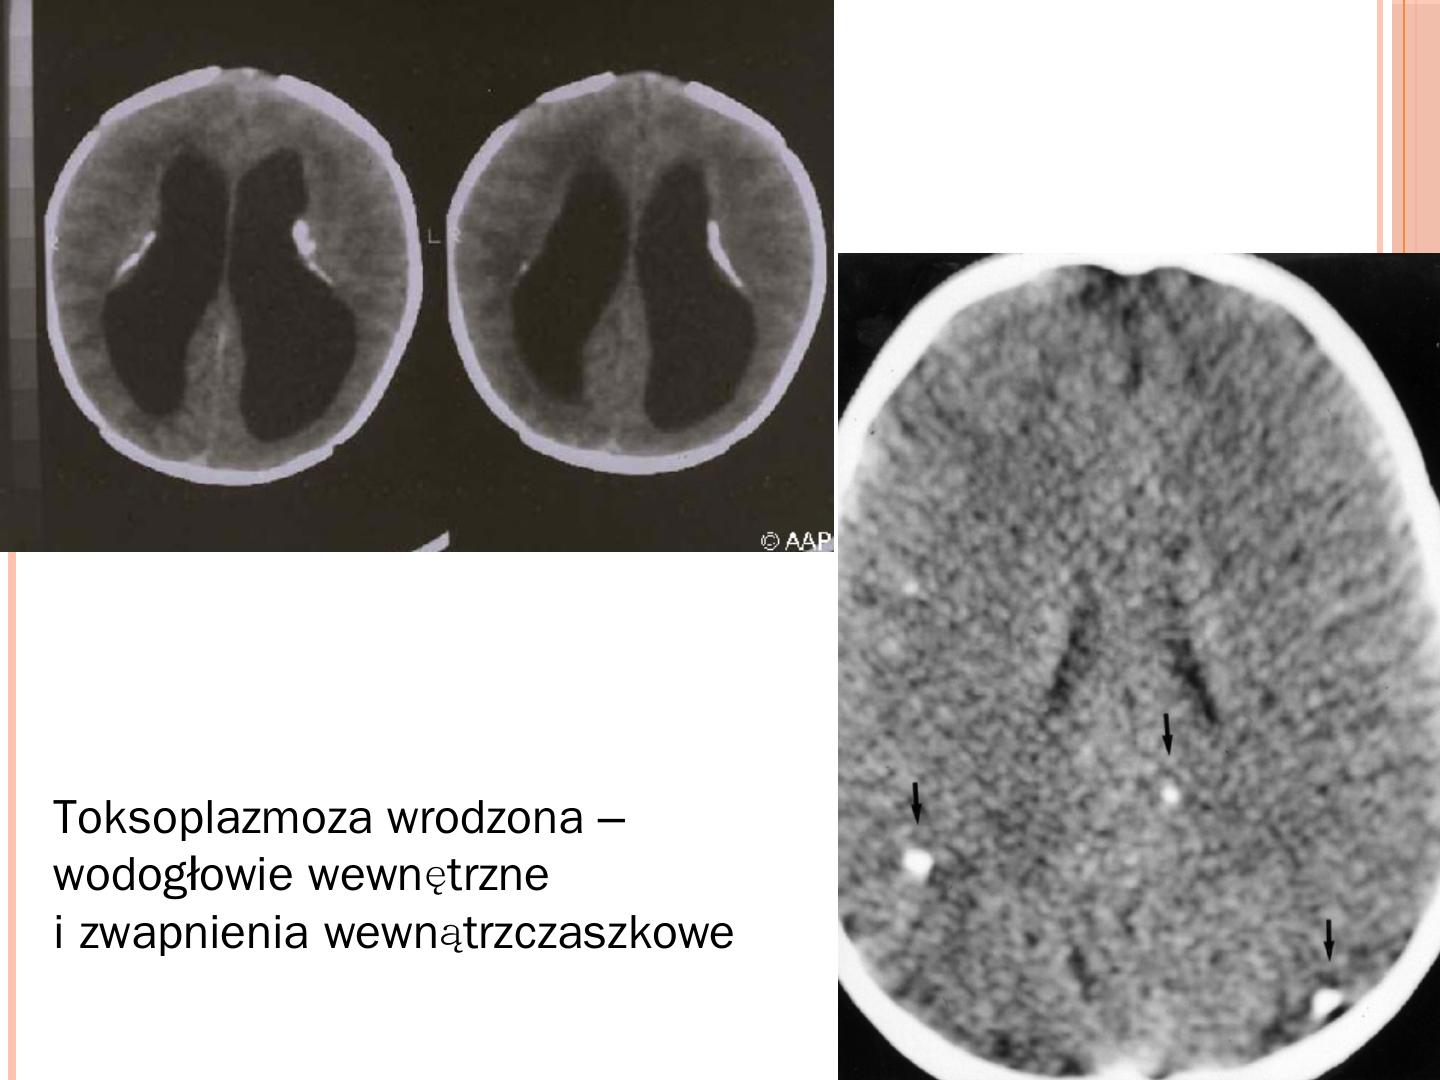

Ewa Majda-Stanisłąwska. Mikroorganizmy powodujące zakażenia wrodzone. TORCH. Toksoplazmoza; Różyczka; Cytomegalia; Herpes simplex wirus typ 2.